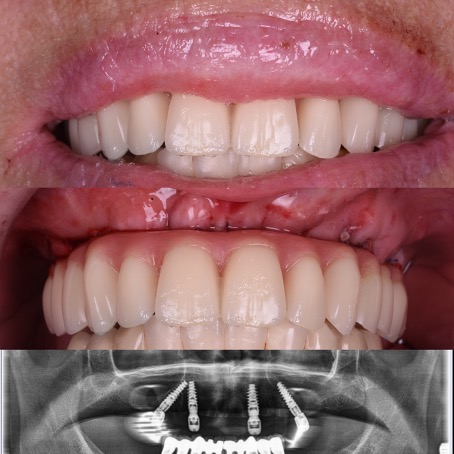

All-on-4®

Édentation totale de la mâchoire – restauration complète fixe avec des implants dentaires

Avant

Après

Selon les techniques modernes de mise en charge immédiate pour les patients édentée, nous avons la possibilité, dans la plupart des cas, d’offrir des dents fixes aux patients dans la journée.

Le protocole All-on-4® permet de réaliser immédiatement une prothèse fixe avec seulement quatre implants par mâchoire. Les implants du fond sont mis en place avec une inclinaison de 30 à 45 degrés, dans les cas où des dents encore présentes devraient être extraites le tout est fait pendant la même opération, la journée se termine pour le patient avec l’installation des dents fixes dans le 90% des cas. Une prothèse définitive sera réalisée environ 4 mois plus tard.